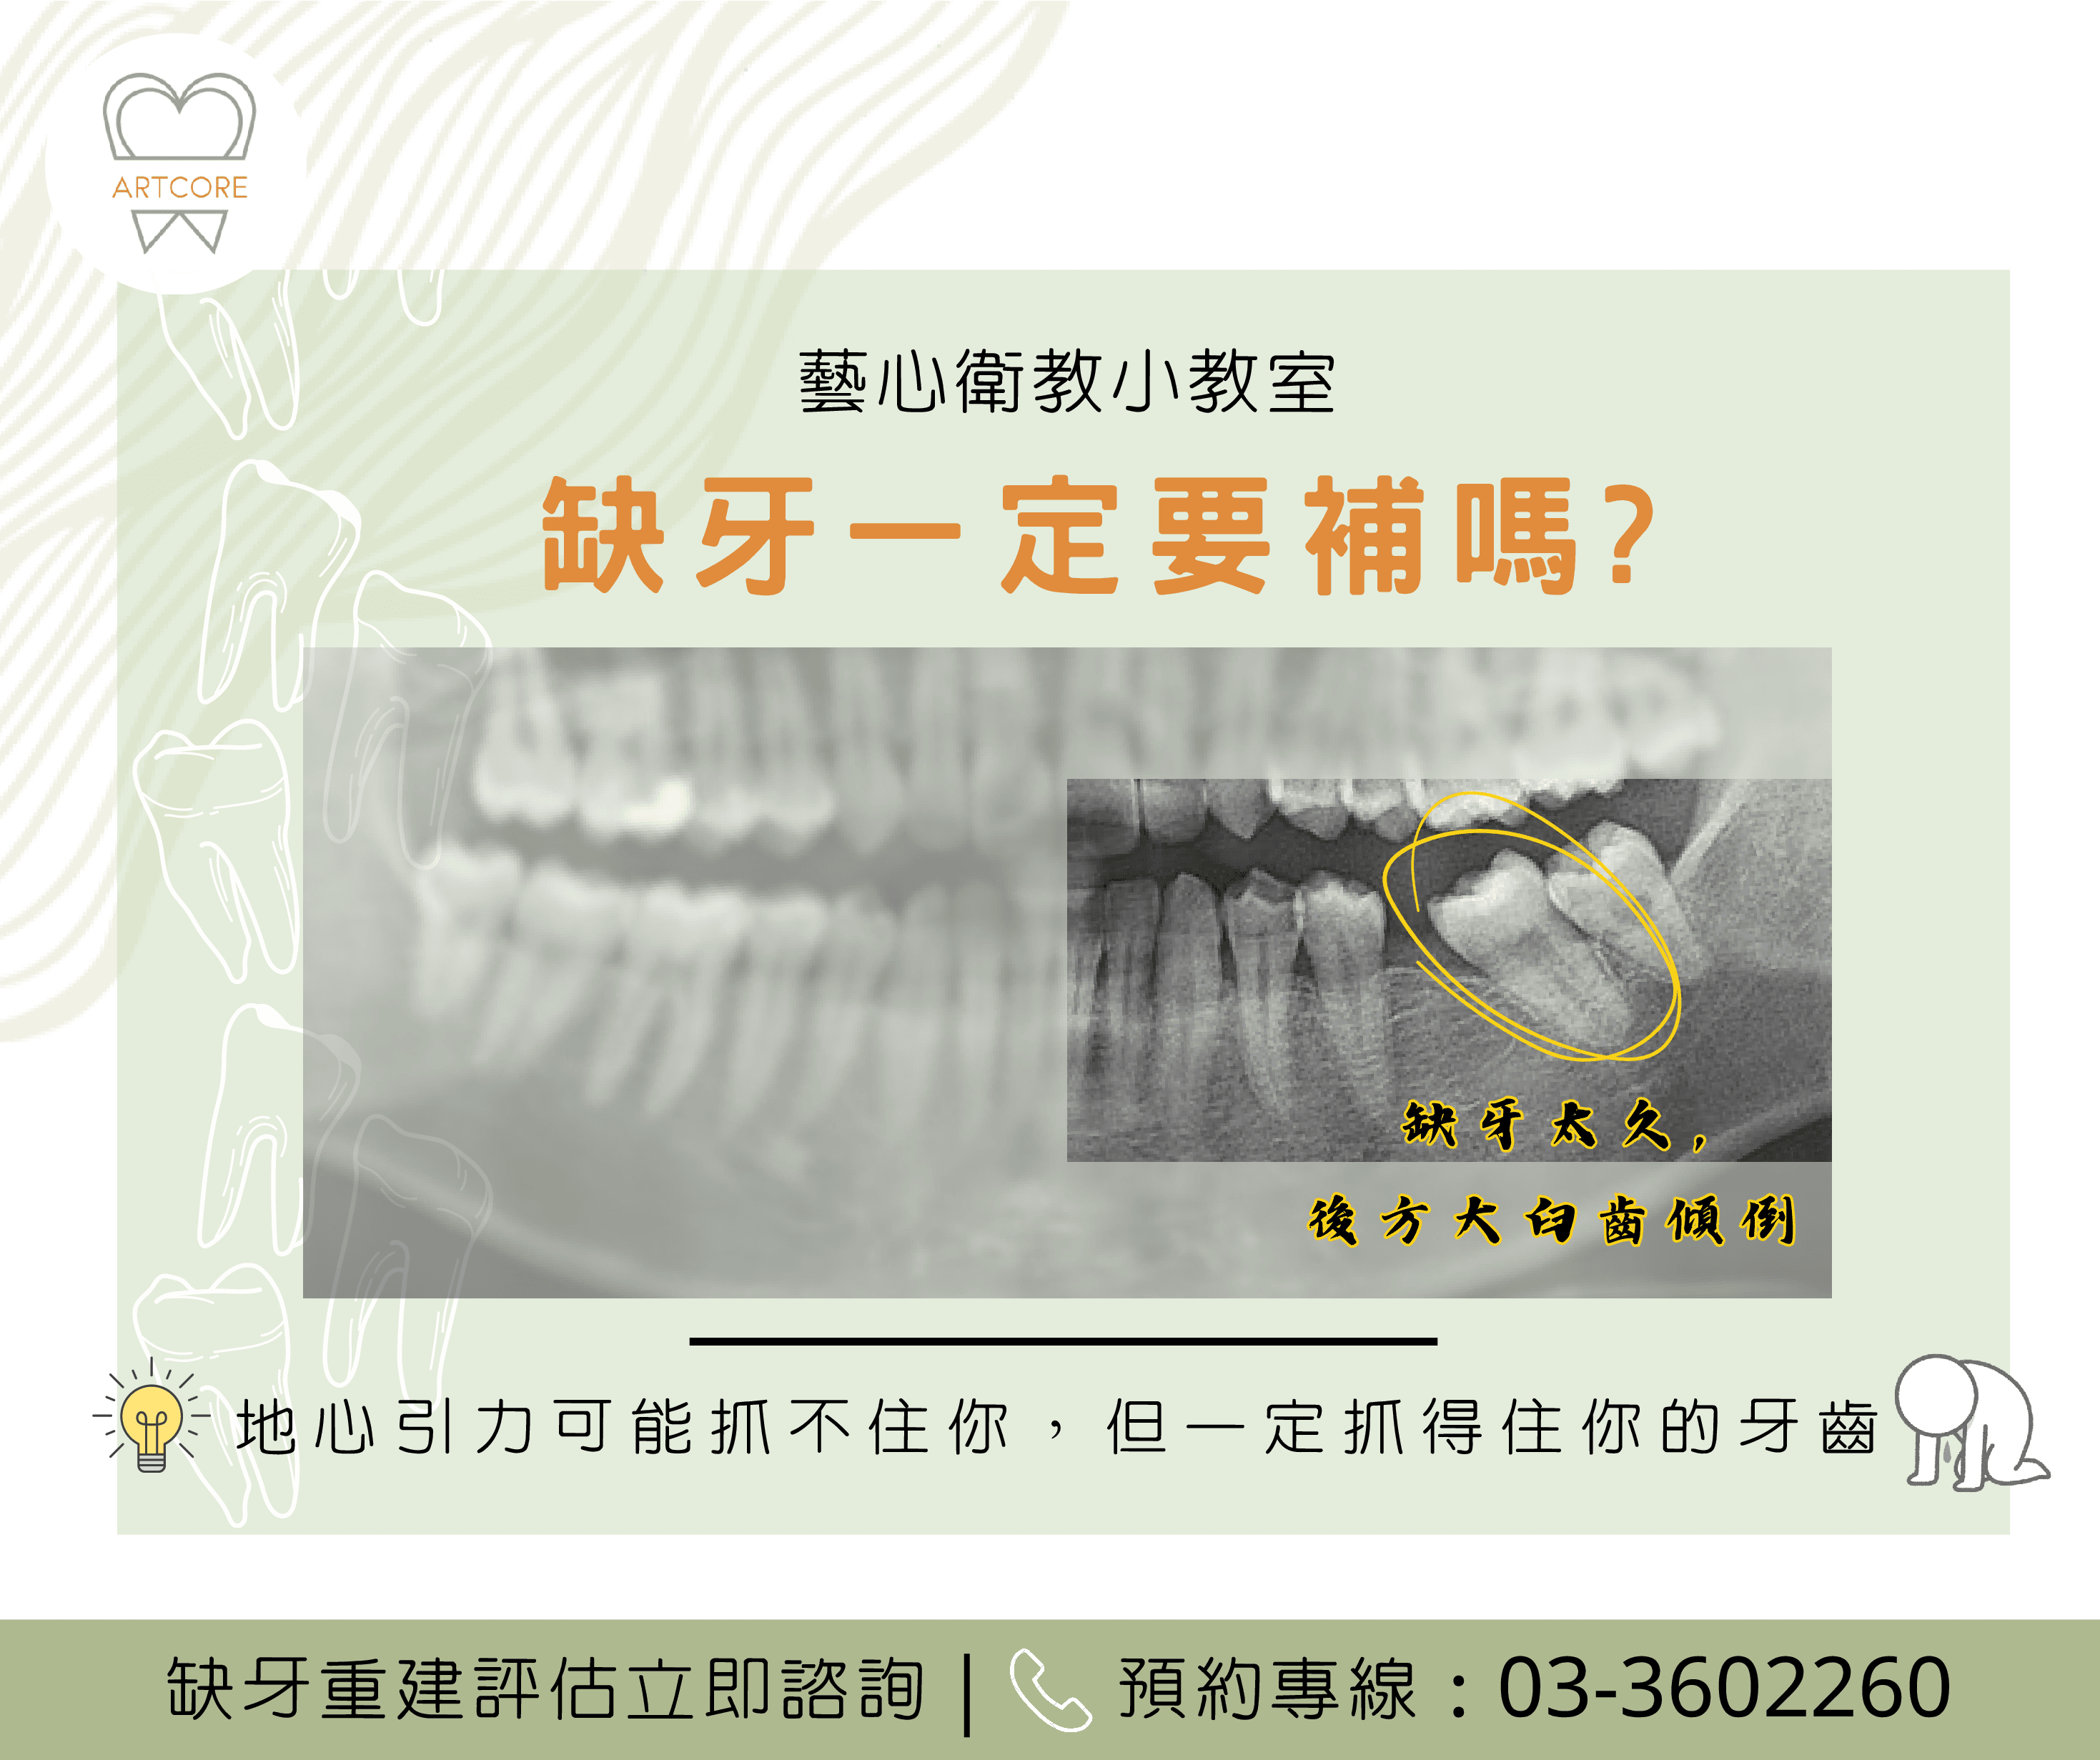

不只要補,還要越快越好 缺牙不只影響美觀自信,也可能造成諸多後遺症 鄰牙位移、傾斜至缺牙處 缺牙處的